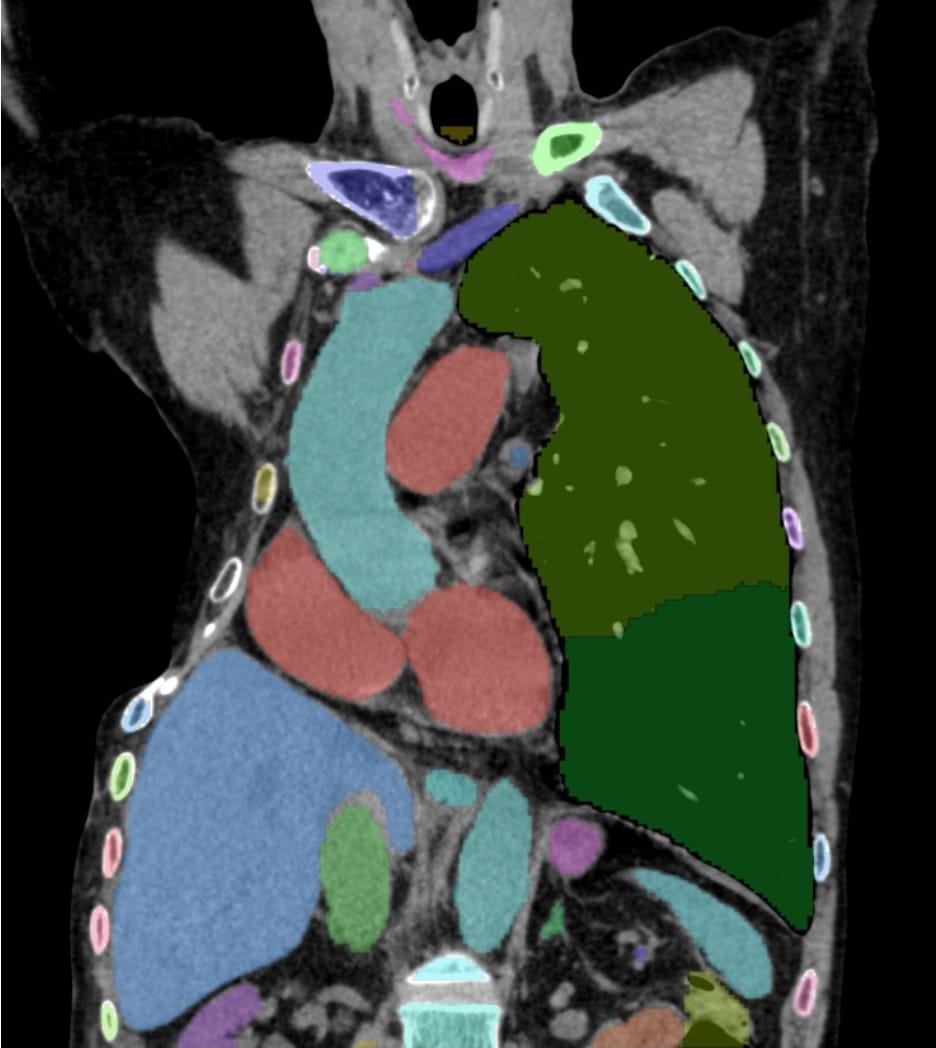

My first Geeking Out post was in Feb 2025, a year back when I wrote about setting up a workstation with two 27 inch screens using a MacMini M4 with 16GB RAM and 256GB hard disk and two 2TB externals SSDs. I have installed them wherever I read scans. I needed to make one more and this time I bought an M4 with 24GB RAM and 512 GB hard disk, so that I could use the Totalsegmentator plugin in OsirixMD, which needs 24GB RAM to run. The CT scan segmentation is just brilliant as this one image shows and it was worth the upgrade of one of my workstations just to be able to do this. Each organ is color coded and labeled (this is a patient of thoracoplasty that I did a Case of the Day of last week)